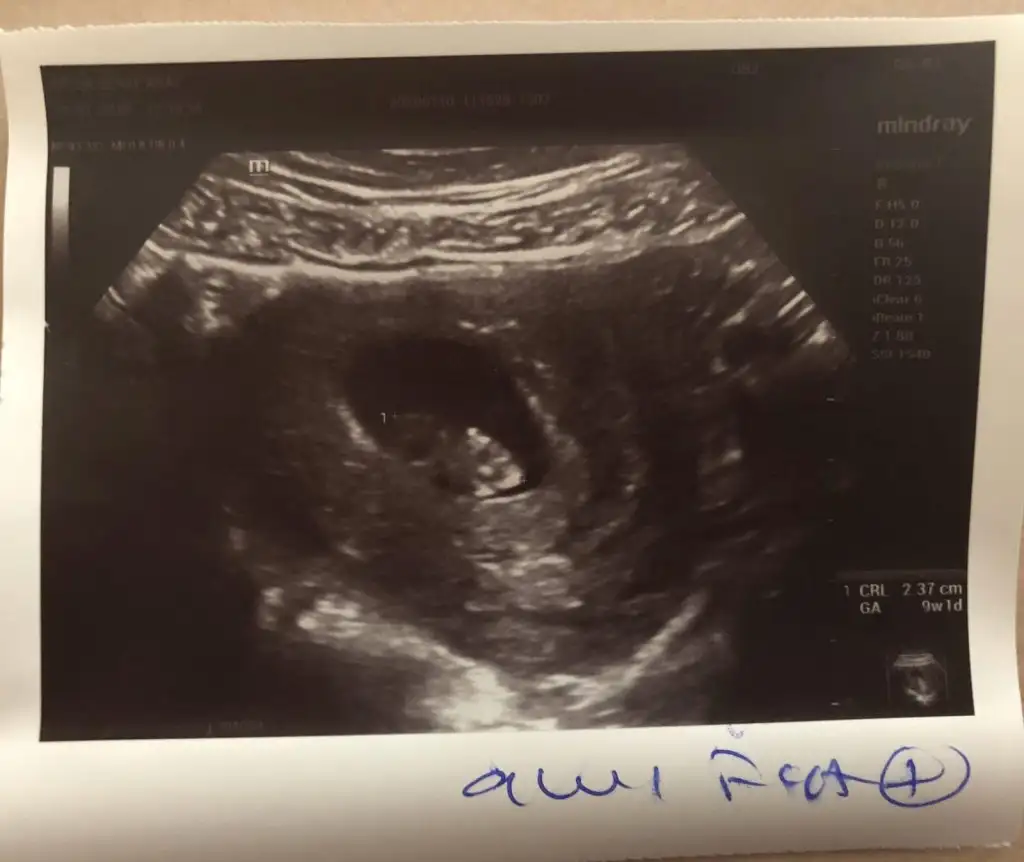

Benimkiler direk ekrandan. Karından ultrason. Acaba cinsiyetleri ne olabilir. 12 haftalıklar burda